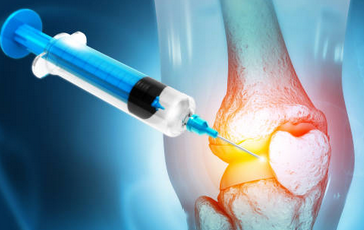

1. 보존적 치료: 무릎에 부담을 줄이기 위해 휴식, 압박, 고정, 얼음치료 등을 합니다. 통증과 염증을 줄이기 위해 진통제나 스테로이드 주사를 사용할 수 있습니다. 허벅지 근육을 강화하기 위해 물리치료나 운동치료를 받을 수 있습니다. 히알루론산 주사를 통해 관절의 윤활작용을 증진시킬 수 있습니다.

2. 봉합술: 찢어진 부위가 혈액이 통하는 반월상 연골의 1/3 범위에 있고, 정도가 심하지 않은 경우에 가능합니다. 관절경을 이용해 찢어진 연골을 바늘로 봉합하는 수술입니다.